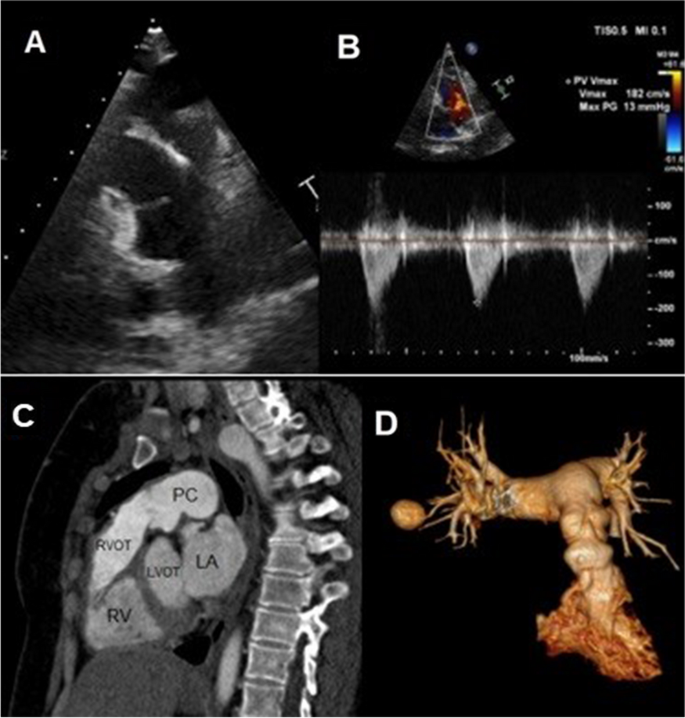

Postoperative echocardiography showed a well-functioning Freestyle pulmonary valve with no residual masses or regurgitation and a peak gradient of 13 mmHg (Fig. 3A, B, supplementary video 3).

A TTE, PSX view, showing well-functioning freestyle valve in the pulmonary position with no regurgitation or residual masses. B CWD on the PV, showing peak gradient of 13 mmHg. C CTPA, sagittal view, showing dilated MPA. D 3D VRT, showing tubular pulmonary conduit with a focal concentric narrowing. TTE, transthoracic echocardiography. PSX, parasternal short axis. CWD, continuous wave Doppler. PV, pulmonary valve. CTPA, computed tomography pulmonary angiography. MPA, main pulmonary artery. VRT, volume-rendered technique

The patient was continued on antibiotics postoperatively for 4 weeks, after which she was discharged to home. On follow-up after 1 year, CT pulmonary angiography showed a well-functioning PV Freestyle (Fig. 3C, D, supplementary videos 4, 5).